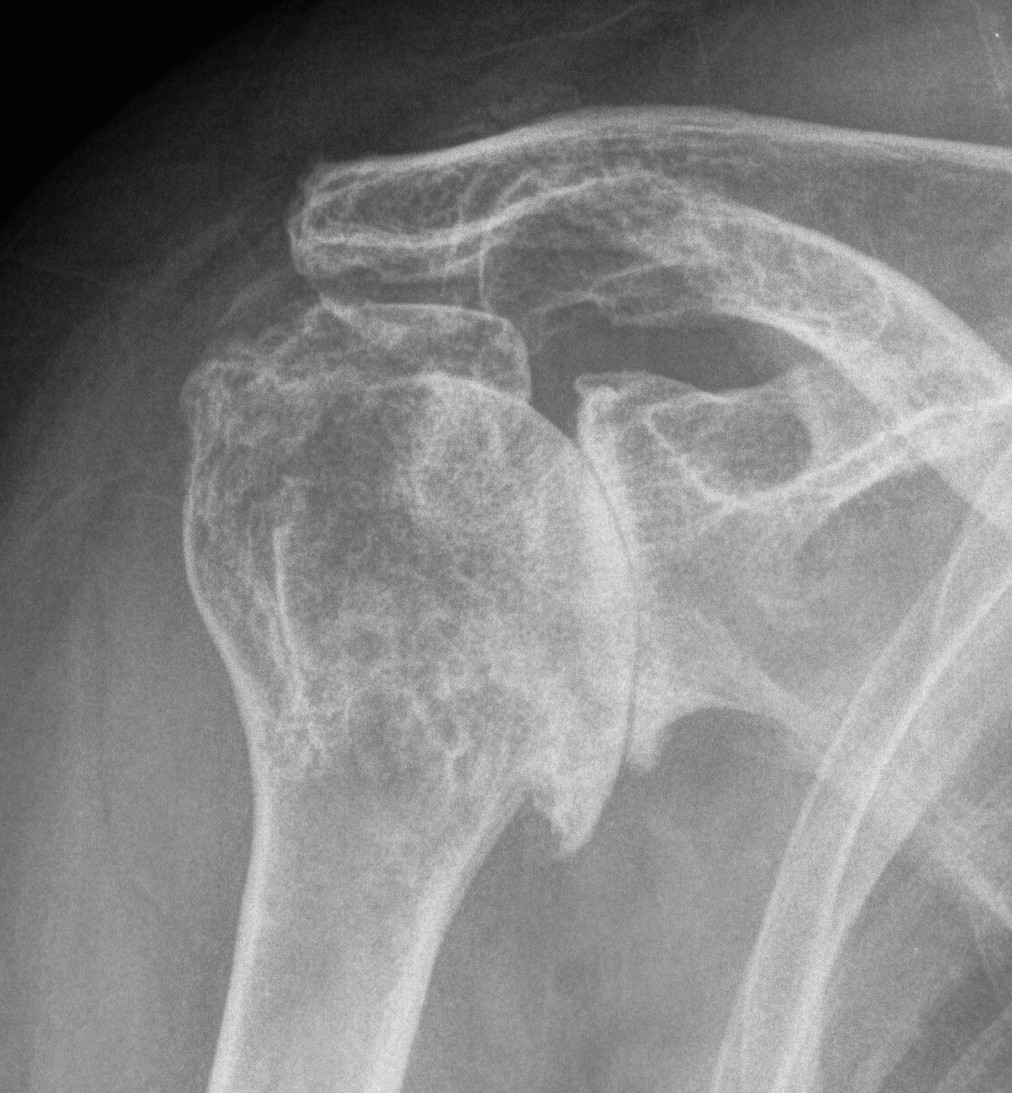

X-ray

Typical changes of OA

1. Teardrop / beard osteophytes on inferior head & glenoid

2. Osteochondral loose bodies

Beard osteophytes

Osteochondral loose body